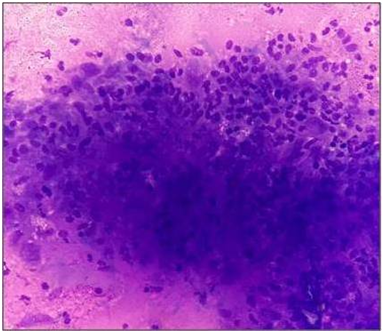

A 50-year-old male presented with a 4-month history of facial swellings in the bilateral maxillary sinus region. The patient was a labourer and belonged to a lower socioeconomic status. He also gave a history of persistent dull ache in the facial bones and orbit along with progressive weight and appetite loss since last one month. However, there was no history of fever, trauma, respiratory, or genitourinary symptoms. His medical history for any major disease or prior surgeries as well as family history was non-contributory. On general physical examination, he was of average built and was anemic. Local examination of the bilateral facial swellings revealed them to be ill-defined, tender, soft and and the overlying skin was slightly erythematous (Figure 1). All other systemic examinations were within the normal limits. His routine hematological investigations revealed microcytic hypochromic blood picture with normal erythrocyte sedimentation rate (ESR). The biochemical and microbiological tests as well as X‑ray chest showed no abnormality. Endoscopic examination showed no nasal mass or polyp. A provisional clinical diagnosis of chronic sinusitis was made and the patient was put on conservative management. However, the patient did not respond to the course of antibiotics as the swellings progressively grew in size. He was revisited again and fine needle aspiration cytology (FNAC) of bilateral maxillary sinus region swellings was performed to arrive at a diagnosis this time. FNAC done from these swellings yielded blood mixed mucoid aspirate and the smears examined showed numerous epithelioid cell granulomas along with intact and degenerated inflammatory cells. Occasional multinucleated langhans type of giant cells and focal necrosis was also seen (Figure 2). Special stain for tubercle bacilli (Ziehl-Neelsen stain) showed few acid fast bacilli (AFB) thus, establishing the diagnosis of bilateral maxillary sinus TB (Figure 3). On further investigations, mantoux test came out to be positive. His sputum and urine were also tested for AFB. However, they were negative for it. The patient was started on a 6-month course of antituberculous treatment (ATT) with rifampicin, isoniazid, pyrazinamide, and ethambutol. He was under regular monthly follow-up, and there was no clinical or laboratory evidence of recurrence or any fresh complaints even after 1 year of treatment.

Figure 2 Epithelioid cell granuloma against a necrotic background (Giemsa, x200).